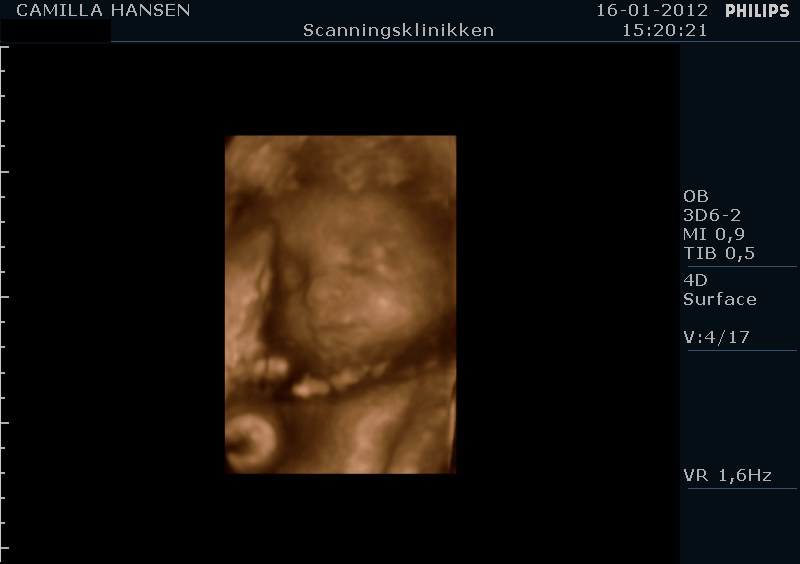

babymus77 skriver:

Ejj hvor er de gode og tydelige 3D billederne:-) Jeg skal her d 20 april, men ved ikk om det er for tidlig?? Er der 26+3???

tak det er nogle rigtige gode billeder.....

jeg var i uge 28 eller 29 og det må helst ikke være sener ind det.

jeg fødte d.26/3 2012 og billederne passer hun ser ud som på billederne.

3d/4d scanninger er helt klart noget jeg vil anbefale.